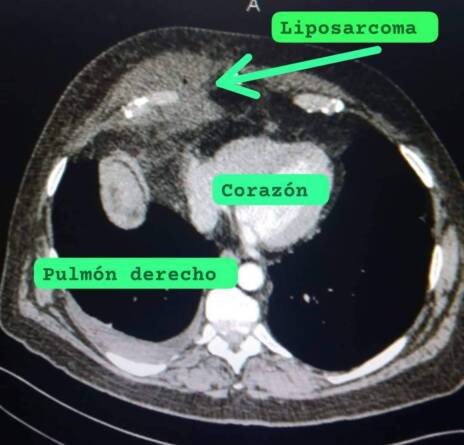

Este riesgoso proceder quirúrgico fue realizado por un equipo multidisciplinario del Hospital Oncológico “Celestino Hernández Robau” con el objetivo de extraer un liposarcoma a un paciente de 69 años, que ya se recupera de manera satisfactoria.

Se trata de la segunda cirugia torácica de alta complejidad y muy riesgosa que se realiza en Villa Clara para extraer un liposarcoma de células redondas de pared costal derecha.

El tumor, de cuatro libras aproximadamente, involucraba desde la quinta hasta la octava costilla, el hemidiafragma derecho, el cuerpo derecho del esternón, la grasa pericardica y una porción del lóbulo medio del pulmón derecho.